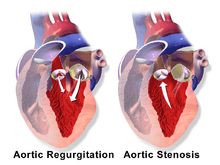

Aortic insufficiency (AI), also known as aortic regurgitation (AR), is the leaking of the aortic valve of the heart that causes blood to flow in the reverse direction during ventricular diastole, from the aorta into the left ventricle. As a consequence the cardiac muscle is forced to work harder than normal.[1]

The mechanism of aortic insufficiency (AI), comprises the pressure in the left ventricle falling below the pressure in the aorta, the aortic valve is not able to completely close. This causes a leaking of blood from the aorta into the left ventricle. This means that some of the blood that was already ejected from the heart is regurgitating back into the heart. The percentage of blood that regurgitates back through the aortic valve due to AI is known as the regurgitant fraction. This regurgitant flow causes a decrease in the diastolic blood pressure in the aorta, and therefore an increase in the pulse pressure. Since some of the blood that is ejected during systole regurgitates back into the left ventricle during diastole, there is decreased effective forward flow in AI.[6][7]

Physiology in individuals with a normally functioning aortic valve, the valve is only open when the pressure in the left ventricle is higher than the pressure in the aorta. This allows the blood to be ejected from the left ventricle into the aorta during ventricular systole. The amount of blood that is ejected by the heart is known as the stroke volume. Under normal conditions, >50% of the blood in a filled left ventricle is ejected into the aorta to be used by the body. After ventricular systole, the pressure in the left ventricle decreases as it relaxes and begins to fill up with blood from the left atrium. This relaxation of the left ventricle (early ventricular diastole) causes a fall in its pressure. When the pressure in the left ventricle falls below the pressure in the aorta, the aortic valve will close, preventing blood in the aorta from going back into the left ventricle.[14][15][16]

The hemodynamic sequelae of AI are dependent on the rate of onset of AI.[26] Therefore, can be acute or chronic as follows: